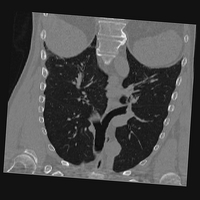

Exp. 3: Adult thorax data: To show the versatility of our approach we also apply it to adult thorax scans. For this experiment no organ specific training is performed but the whole volume is used. We evaluate reconstruction performance similar to Exp. 1 and Ti^^subscript𝑇𝑖\hat{T_{i}} prediction performance when ΩΩ\Omega is projected on an external plane, comparable to X-Ray examination using C-Arms. The latter provides insights about our method’s performance when applied to interventional settings in contrast to motion compensation problems. 60 healthy adult thorax scans were randomly selected, 51 scans used for ΩtrainsubscriptΩ𝑡𝑟𝑎𝑖𝑛\Omega_{train} and nine scans used for ΩvalidationsubscriptΩ𝑣𝑎𝑙𝑖𝑑𝑎𝑡𝑖𝑜𝑛\Omega_{validation}. Each scan is intensity normalised and resampled in a volume of 200×200×200200200200200\times 200\times 200 with spacing 1mm×1mm×1mm1𝑚𝑚1𝑚𝑚1𝑚𝑚1mm\times 1mm\times 1mm. Using the Fibonacci sampling method, 25 sampling plane of size 200×200200200200\times 200, evenly spaced between -50 and +50, were rotated over 500 normals. Training took approximately 20 hours for 60 epochs. Fig. 4c shows an example reconstruction result gaining 28dB PSNR with additional SVR. Ti^^subscript𝑇𝑖\hat{T_{i}} prediction takes approx. 20 ms/slice for this data.

Figure 4: (a): Comparison of a single slice from raw low-dose thorax CT data; (b): reconstruction based on SVRNet Ti^^subscript𝑇𝑖\hat{T_{i}} regression; (c): SVR initialized with SVRNet transformations after four iterations of SVR; (d): PSNR of (b) and (c) compared to (a). (e): shows a projection of an unseen pathological test CT volume as DRR and (e) shows a DRR at the location predicted by our method when presented with the image data in (e).

We use Siddon-Jacobs ray tracing [15] to generate Digitally Reconstructed Radiographs (DRRs) from the above described data. For training, we equally sample DRRs on equidistant half-spheres around 51 CT volumes at distances of 80cm, 60cm, and 40cm, between 90superscript90-90^{\circ} and 90superscript9090^{\circ} around all three co-ordinate axes. For validation, we generate 1000 DRRs with random rotation parameters within the bounds of the training data at 60cm distance from the volumetric iso-centre. We trained on healthy volunteer data and tested on nine healthy and ten randomly selected pathological volumes (eight lung cancer and two spinal pathologies). Our approach is able to predict DRR transformations relative to the trained reference co-ordinate system with an average translation error of 106mm and 5.6superscript5.65.6^{\circ} plane rotation for healthy patients, and 130mm and 7.0superscript7.07.0^{\circ} average error for pathological patients. An example is shown in Fig. 4e,f. Note that these values are good enough to robustly initialize intensity-based registration refinement. SVRNet prediction can be improved by generating a denser training data set, in particular, in more equidistant half-spheres.